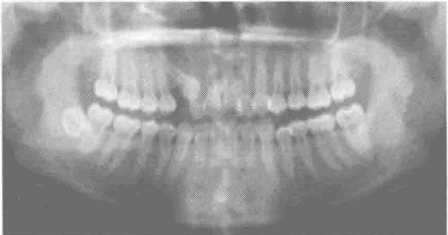

偏颌畸形的牙颌模型诊断是怎么样的 牙颌模型检查与分析可以提供牙齿位置与排列、牙弓形态与对称性、上下牙弓间关系与协调性、咬合关系等信息,是诊断牙颌不对称畸形不可缺少的资料。... 牙齿矫正 鲜清怡 671 2024-03-26

牙颌模型检查的作用是什么 牙颌模型检查与分析可以提供牙齿位置与排列、牙弓形态与对称性、上下牙弓间关系与协调性、咬合关系等信息,是诊断牙颌不对称畸形不可缺少的资料。... 牙齿矫正 admin 608 2023-10-24